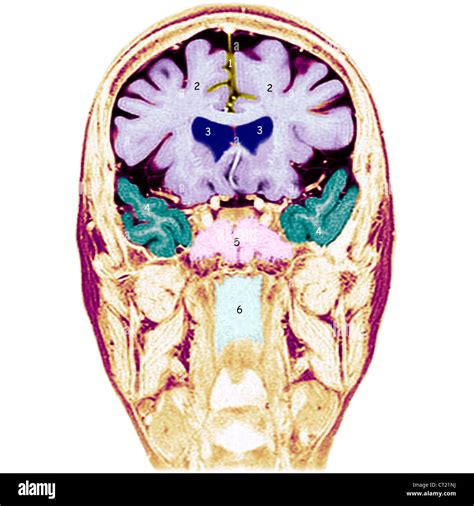

The human brain is a complex and fascinating organ, with intricate structures that facilitate various cognitive functions. One of the most notable features of the brain is the Medial Longitudinal Fissure (MLF), a deep groove that runs along the midline of the brain, separating the two cerebral hemispheres. This fissure plays a crucial role in the brain's anatomy and function, and understanding it can provide valuable insights into neurological health and disorders.

The Medial Longitudinal Fissure is a prominent landmark in the brain's anatomy. It extends from the frontal lobe to the occipital lobe, dividing the brain into left and right hemispheres. This division is not just physical; it also reflects functional specialization. The left hemisphere is often associated with logical thinking, language, and analytical skills, while the right hemisphere is linked to creativity, spatial awareness, and emotional processing.

The MLF is lined with the corpus callosum, a thick band of nerve fibers that connect the two hemispheres. The corpus callosum allows for communication between the hemispheres, enabling coordinated brain function. This structure is essential for integrating information and ensuring that both hemispheres work together seamlessly.

Several imaging techniques are used to visualize the Medial Longitudinal Fissure and the corpus callosum. These techniques provide detailed images of the brain's structures, aiding in diagnosis and treatment planning. Some of the most commonly used techniques include:

• Magnetic Resonance Imaging (MRI): MRI provides high-resolution images of the brain, allowing for detailed visualization of the MLF and the corpus callosum. It is particularly useful for detecting structural abnormalities and assessing brain health.

• Computed Tomography (CT) Scan: CT scans use X-rays to create cross-sectional images of the brain. While not as detailed as MRI, CT scans are useful for detecting fractures, tumors, and other structural issues.

• Diffusion Tensor Imaging (DTI): DTI is a specialized MRI technique that maps the diffusion of water molecules in the brain. It provides insights into the integrity of white matter tracts, including the corpus callosum, and can detect abnormalities that may not be visible on standard MRI.